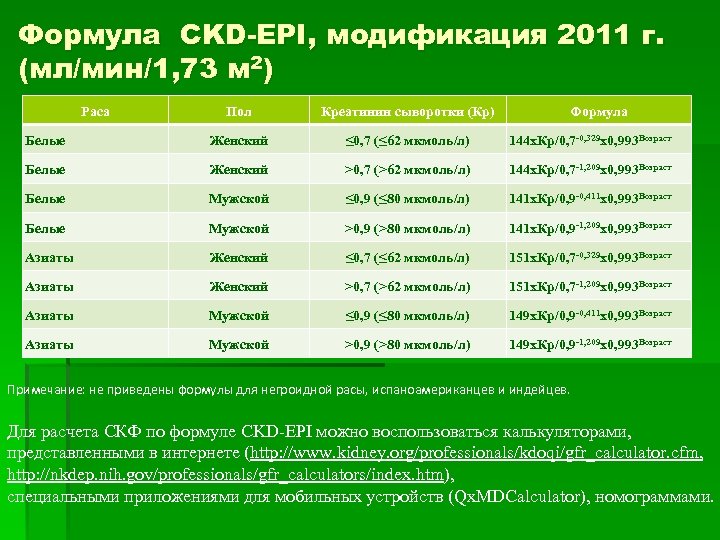

Формула CKD-EPI, модификация 2011 г. (мл/мин/1, 73 м 2) Раса Пол Креатинин сыворотки (Кр) Формула Белые Женский ≤ 0, 7 (≤ 62 мкмоль/л) 144 х. Кр/0, 7 -0, 329 х0, 993 Возраст Белые Женский >0, 7 (>62 мкмоль/л) 144 х. Кр/0, 7 -1, 209 х0, 993 Возраст Белые Мужской ≤ 0, 9 (≤ 80 мкмоль/л) 141 х. Кр/0, 9 -0, 411 х0, 993 Возраст Белые Мужской >0, 9 (>80 мкмоль/л) 141 х. Кр/0, 9 -1, 209 х0, 993 Возраст Азиаты Женский ≤ 0, 7 (≤ 62 мкмоль/л) 151 х. Кр/0, 7 -0, 329 х0, 993 Возраст Азиаты Женский >0, 7 (>62 мкмоль/л) 151 х. Кр/0, 7 -1, 209 х0, 993 Возраст Азиаты Мужской ≤ 0, 9 (≤ 80 мкмоль/л) 149 х. Кр/0, 9 -0, 411 х0, 993 Возраст Азиаты Мужской >0, 9 (>80 мкмоль/л) 149 х. Кр/0, 9 -1, 209 х0, 993 Возраст Примечание: не приведены формулы для негроидной расы, испаноамериканцев и индейцев. Для расчета СКФ по формуле CKD-EPI можно воспользоваться калькуляторами, представленными в интернете (http: //www. kidney. org/professionals/kdoqi/gfr_calculator. cfm, http: //nkdep. nih. gov/professionals/gfr_calculators/index. htm), специальными приложениями для мобильных устройств (Qx. MDCalculator), номограммами.